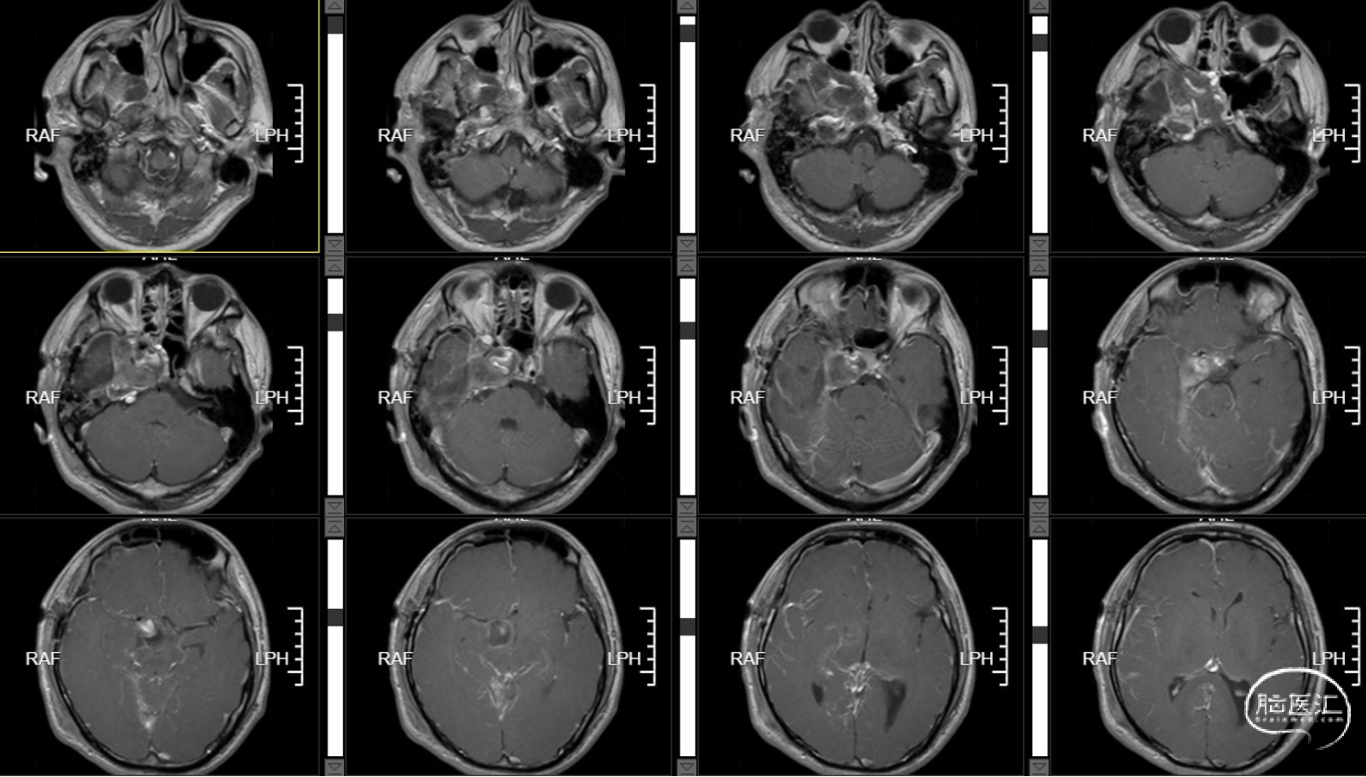

术后T1